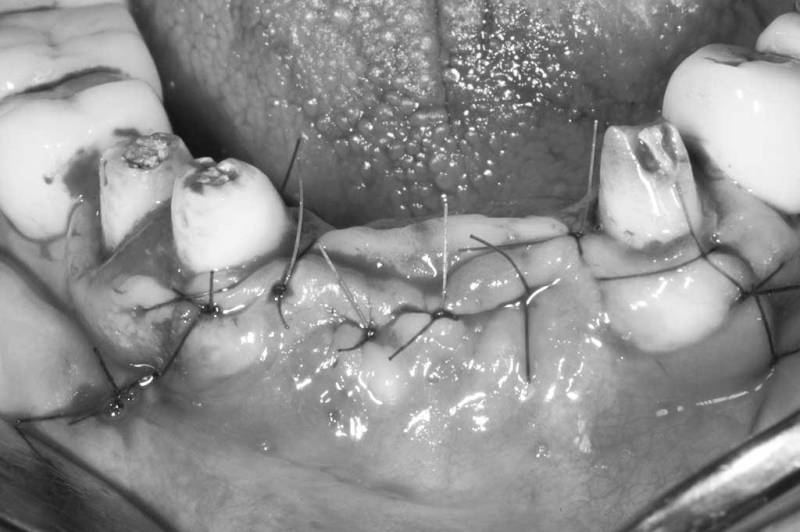

骨脊增厚術術後